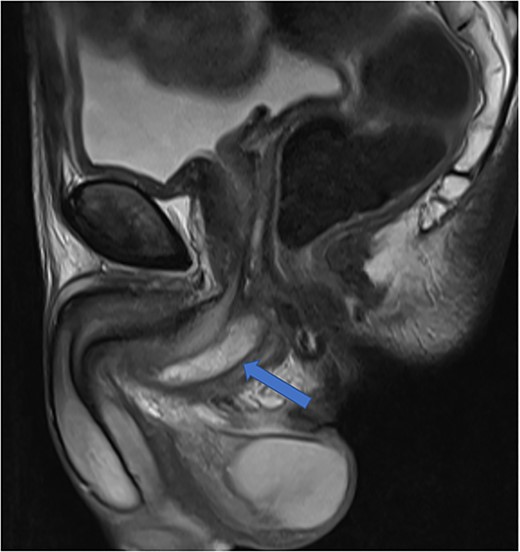

The patient was reviewed again a week later. On examination, a tender perineal mass extending into his posterior scrotum had developed. Again, there were no perianal skin abnormalities on examination. He was put on intravenous antibiotics, and a repeat MRI of his pelvis was organized. This revealed a persistent perineal collection, in proximity with, but not involving, the external anal sphincter, as well as the bulbar urethra and scrotum (Fig. 4).

Case 2: coronal and axial T2-weighted images demonstrating the collection (red and green arrows) significantly compressing the urethra and corpus spongiosum (yellow arrow) to the right of the midline, and close to, but not involving, the anal sphincter (blue arrow).